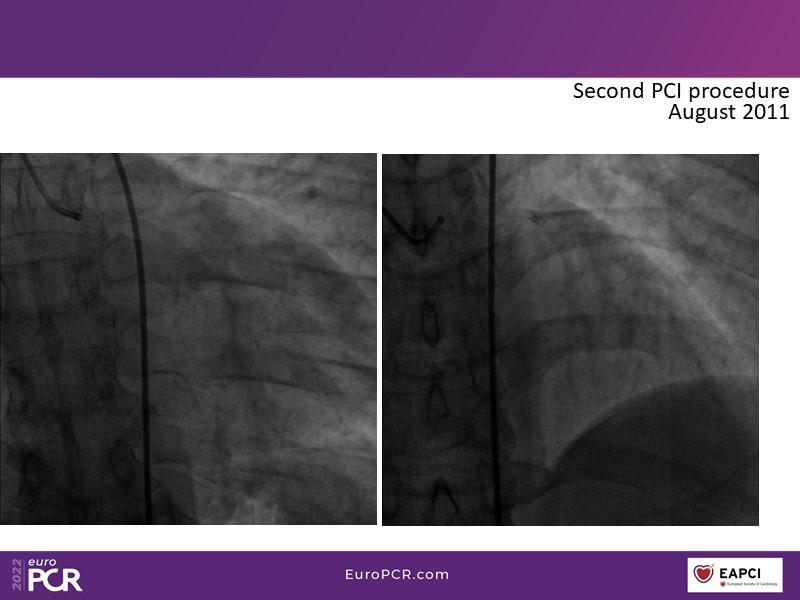

This EuroPCR 2022 session aims to show, based on real-life cases, that even complex coronary disease can be treated without the need for permanent coronary stents. Learn how to prepare the vessel, deliver the therapy, and assess immediate outcomes after "DCB-alone" PCI, discuss de novo, small vessels, and in-stent restenosis cases with follow-up, define what may be an optimal long-term result, refresh the scientific bases, and understand the clinical benefits and safety of paclitaxel DCBs.

- To know how to prepare the vessel, deliver the therapy and evaluate the immediate results after "DCB-alone" PCI

- To discuss de novo, small vessels and in-stent restenosis cases with follow-up and define what may be an optimal long-term result